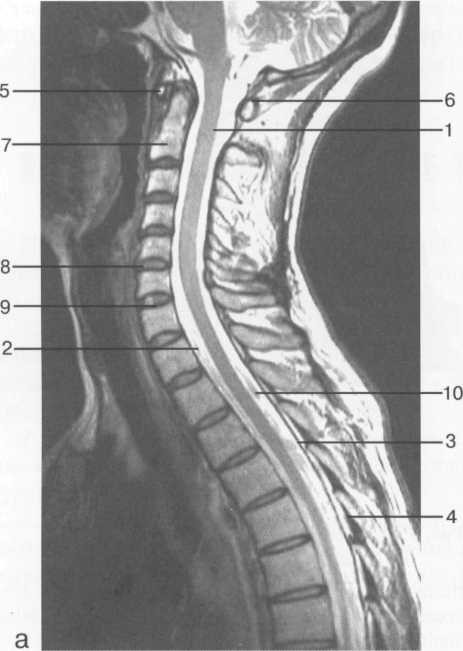

МРТ исследования дают широкую возможность исследовать  все структуры спинного мозга в разных плоскостях. ( рис. 37-41 )

Рис. 38. МРТ. Срединное сагиттальное изображение шейного отдела позвоночника.

а-Т2-ВИ;б-Т1-ВИ.

1 -- спинной мозг; 2 -- субарахноидальное пространство; 3 -- дуральный мешок (задняя стенка); 4 -- эпидуральное пространство; 5 -- передняя дуга С1; 6 -- задняя дуга С1; 7 -- тело С2; 8 -- межпозвонко­вый диск; 9 -- гиалиновая пластинка; 10 -- артефакт изображения; 11 -- остистые отростки позвонков; 12 -- трахея; 13 -- пищевод.